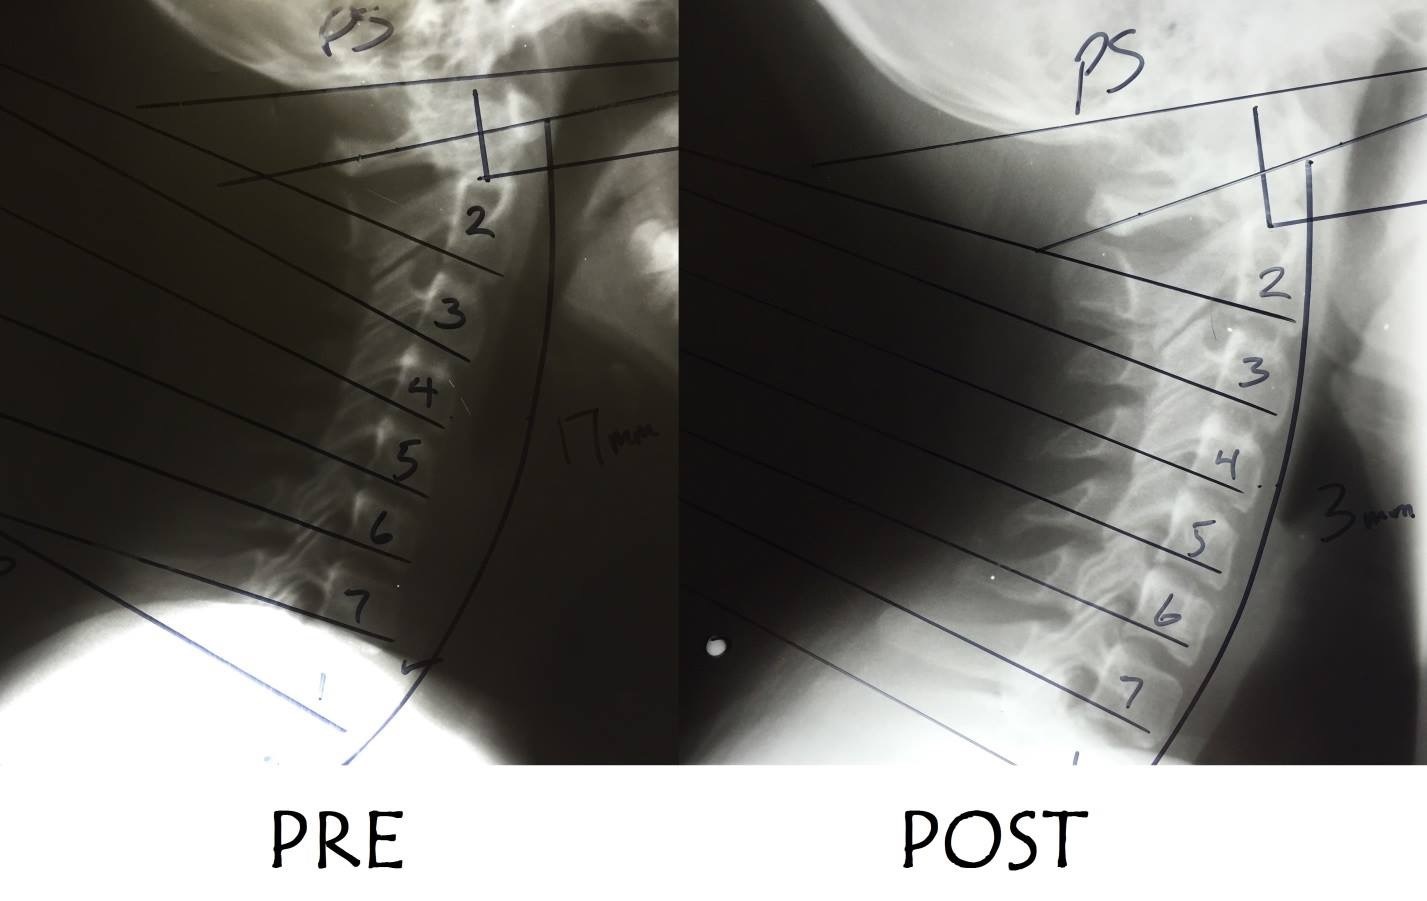

ストレートネックは治る?

ストレートネックは治る?